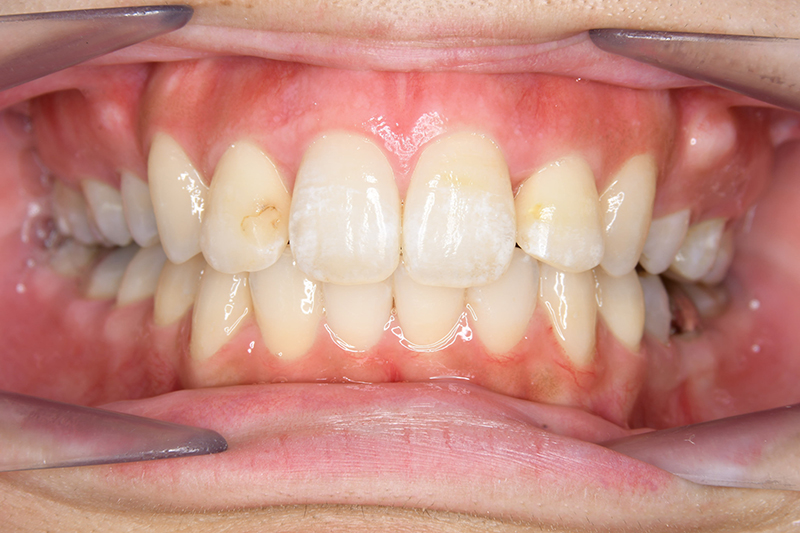

動的治療終了時

FP・IOP

口腔内所見 over jet 11.5mm、over bite 5.5mm、右側臼歯関係Full ClassⅡ級、左側end onⅡ級、上顎顎歯列はテーパー型であり、上顎中切歯は押し出されるように大きく唇側傾斜していた。下顎前歯部は叢生を呈しており、左下5は歯冠長が短く半埋伏していた。

批評・予后 上顎前歯の可及的な後退と臼歯関係のⅡ級を保つためにアンカレッジコントロールはmaximumとしTADを使用してスライディングメカニクスにて前歯遠心移動を行った。また下顎はリンガルからのアプローチであったためその特性を生かし、臼歯のアップライトを速やかに達成して左下5の配列も予定通り行えた。また大幅な前歯の後退に伴い、軟組織の大幅な改善が認められたように思う。